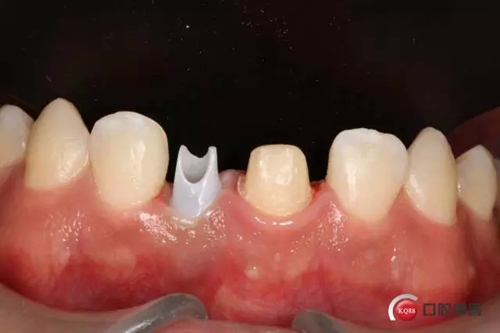

種植后修復(fù),我們要把握每一個細(xì)節(jié),比色,轉(zhuǎn)移桿的就位,我們必須把臨床做好,技工師傅才會給我們做出好的修復(fù)體,減少一些不必要的失誤,首先術(shù)前的檢查是必要一步 ,再是器械的準(zhǔn)備使我們臨床操作有條不紊,術(shù)前拍照,o-bite取咬合記錄,消毒修復(fù)術(shù)區(qū),旋出愈合基臺,生理鹽水沖洗袖口,拍照袖口,安放合適轉(zhuǎn)移桿,拍X線見轉(zhuǎn)移桿就為良好,硅橡膠取模,術(shù)后旋回愈合基臺,拍照比色。

藻酸鹽對頜取模,超硬石膏灌注。發(fā)加工廠,與技工溝通注意事項(xiàng),等修復(fù)體做好后,檢查模型。是否就位,是否密合,預(yù)約患者復(fù)診戴牙,消毒修復(fù)區(qū),旋出愈合基臺,定位器指導(dǎo)安放修復(fù)基臺,試戴冠,調(diào)磨鄰接及 咬合至合適,拋光,患者滿意,加力扳手加力至30N,拍X片見就位良好,特芙蓉及暫封膏封中央螺絲孔,聚羧酸鋅粘固劑粘固,或是樹脂水門汀粘固,清理多余粘結(jié)劑,光固化樹脂封螺絲孔,拋光。術(shù)后注意隨訪。